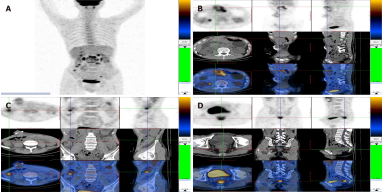

体格检查显示,患者体温36.6℃,心率78bpm,呼吸频率20次/min,血压125/60mmHg。骨瘦如柴,腹部见舟状骨。收缩的横结肠位于上腹部。实验室检查中,血液分析显示贫血,血红蛋白水平为11.1g/dL。血小板计数正常,生化和血浆电解质无明显变化。血清CEA浓度为4.48ng/mL,CA19-9为762.80u/mL,CA24-2>150.00u/mL。正电子发射断层扫描(PET)和计算机断层扫描(CT)显示毗邻横向造口见一巨大软组织肿块,伴有高水平的糖代谢。腹腔内多发结节,均伴有糖代谢增强。提示胃肠道癌已广泛转移(图2)。

图2. 腹部正电子发射断层扫描图像。A:腹腔内多发性病变,糖代谢增高;B:横向造口附近见巨大软组织肿块,伴高水平的糖代谢;C:升结肠葡萄糖代谢水平高;D:直肠膀胱壁多发结节,糖代谢水平高